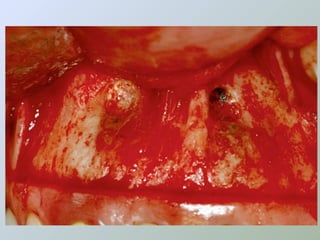

A amputação do ápice radicular deve ser

feita com broca montada em baixa rotação,

com abundante irrigação.

A angulação da broca em relação ao longo eixo

dental deverá ser de 90°, removendo-se desta

maneira o delta apical completamente (BERNARDINELLI

et al. 1994; BRAMANTE; CLÓVIS MARZOLA,BERBERT, 2000 e

MARZOLA, 2000 e 2002),

apesar de ainda alguns autores

serem adeptos da inclinação para vestibular

(SAILER; PAJAROLA, 2000).

Deve-se observar, também, se não há

anomalias anatômicas como: rebarbas,

intercanais, canais acessórios ou fraturas

radiculares a este nível, podendo-se

utilizar solução esterilizada de azul-de-

metileno a 2%, para identificação destas

situações (DEL RIO, 1996) e, mesmo ainda

se ocorre uma infiltração apical em

cavidade para a obturação retrógrada.

(BERNARDINELLI et al., 1994)